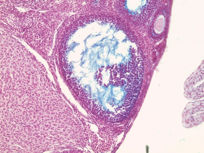

M. Suarez, E. Meinke, V. Romero and Z. Craig, 2026, 'Craig Lab: Mus Musculus Donor APOS001AB Antral Follicles Alcian Blue Slide 1K', https://mother-db.org/MDB0000519, Multispecies Ovary Tissue Histology Electronic Repository, Retrieved: January 15, 2026

Accession #: MDB0000519

Location: follicle

Section thickness: 5 microns

Fixation: Formalde-Fresh Solution

Stain: Light microscopy stain